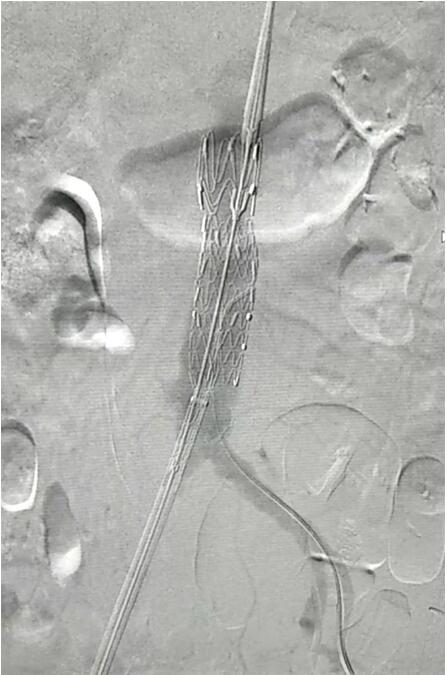

血管介入科行腹主動脈瘤覆膜支架隔絕術(shù)(“褲衩”支架植入)。圖1

患者因腹部搏動性腫塊行成已有4年,伴右下腹疼痛6小時入院,既往有高血壓病史,患者入院后血壓177/96mmHg,醫(yī)護(hù)人員隨即予以控制血壓、止痛處理,CTA檢查提示患者有腎下腹主動脈瘤,合并心 、肝 、肺 、腎等重要臟器疾患,根據(jù) Laplace定律,動脈瘤直徑越大壓力越大,老人動脈脆弱,動脈瘤隨時有破裂的可能性,其危險性大。血管介入科排除各種困難,在麻醉科協(xié)作下行腹主動脈瘤覆膜支架隔絕術(shù)(“褲衩”支架植入),手術(shù)持續(xù)了1個半小時,患者術(shù)后安返病房,麻醉醒后露出了微笑,向醫(yī)務(wù)人員伸出大拇指。